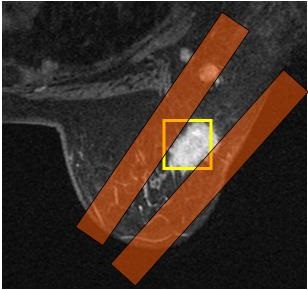

Typically, BREASE is performed after first completing a study of the breast using VIBRANT. BREASE uses a TE-averaged, PRESS spectroscopy acquisition, compatible with the 4-, 7-, or 8-channel Breast coil.

Use these steps to acquire a BREASE spectrum for breast spectroscopy. The spectrum is displayed in the Viewer. MR breast spectroscopy can show if elevated concentrations of the Choline metabolite are present in a lesion.

| Spectrum call out | Description |

|---|---|

| A | Spectrum A is a magnified version of spectrum B. |

| B | Spectrum acquired from BREASE VOI. |

| C | Zoomed spectrum from area D. Note that the zoom factor is fixed. |

| D | Represented by area C (zoomed). It is centered on the choline peak which is located, 3.2 ppm. |

| E | PPM scale. |